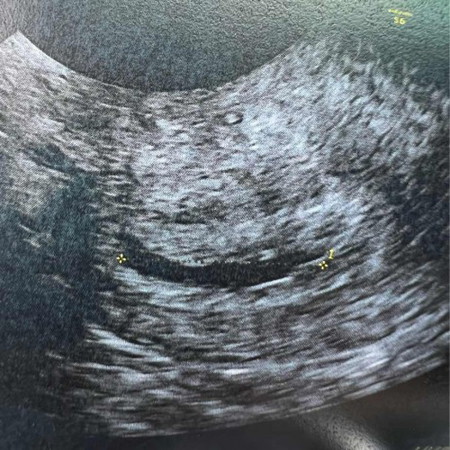

ถุงการตั้งครรภ์ผิดรูป

ท้อง 5 สัปดาห์เจอแต่ถุงการตั้งครรภ์ยังไม่เจอตัวอ่อนถุงการตั้งครรภ์ ลักษณะไม่ค่อยดีมีรูปทรงแบบยาวๆปกติต้องลักษณะกลมๆ แบบนี้จะมีโอกาศได้ลูกไหมคะ